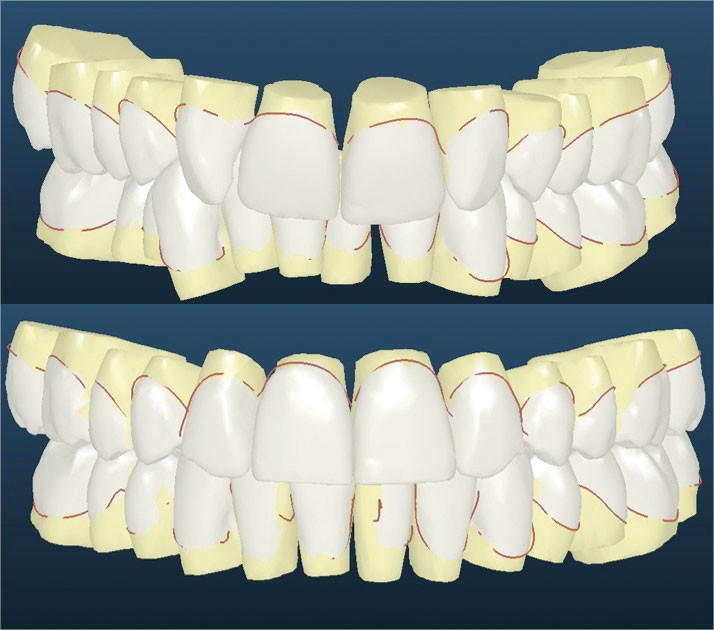

Un appareillage Damon métal a été mis en place, réalisé à partir d’un set up numérique Insignia pour obtenir un contrôle précis des torques et de la forme d’arcade et réduire le temps de finition grâce à un collage indirect très précis.

L’objectif, en utilisant la technique Insignia est de réduire le temps de traitement de 28 à 18 mois avec 12 rendez-vous (fig. 5 à 14).